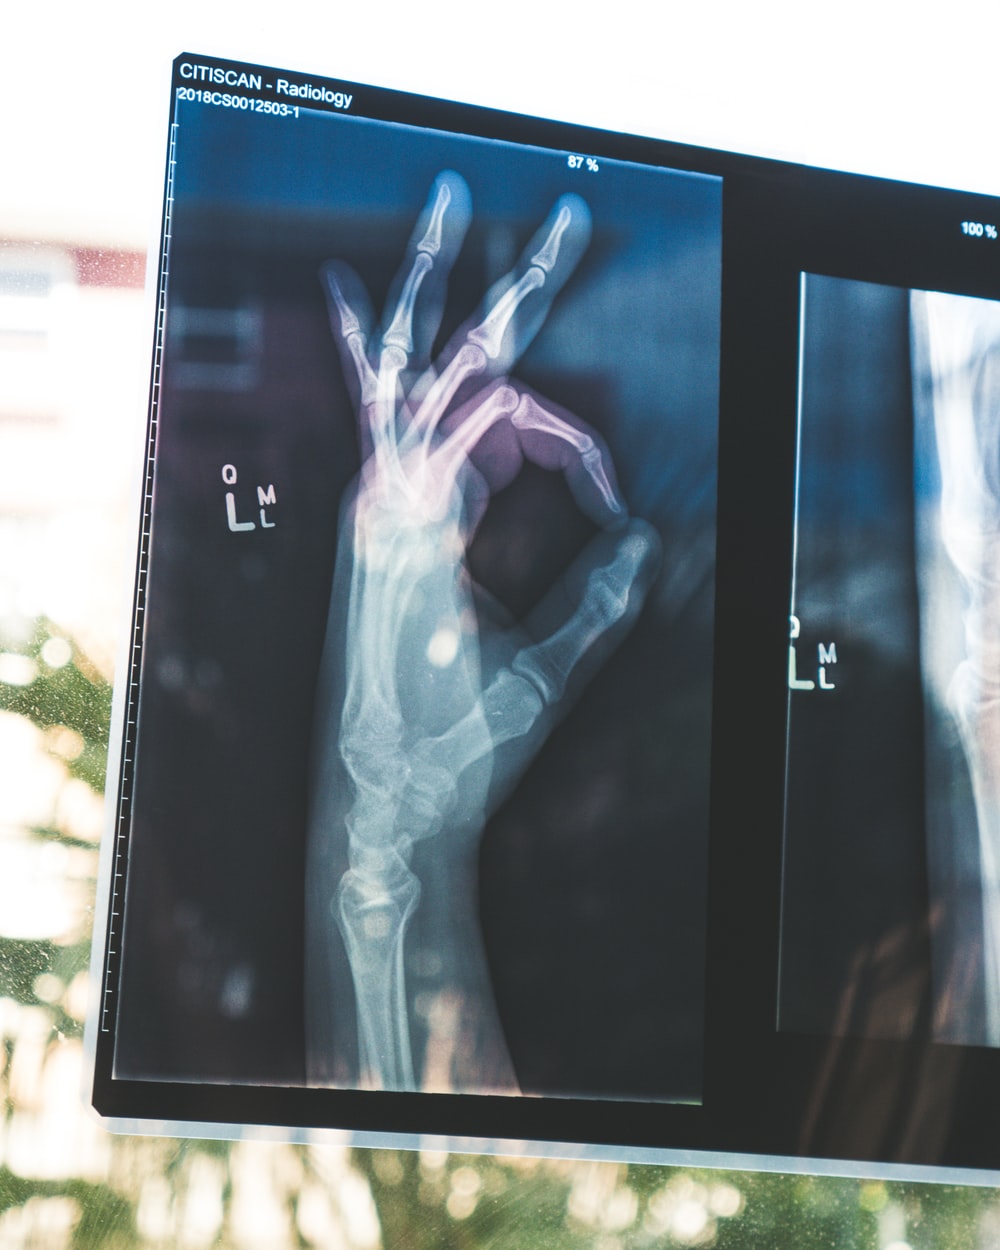

연골은 연골세포와 연골 기질로 이루어진 조직입니다. 연골은 뼈와 뼈사이에 있으며 탄력성이 높아서 주어진 힘에 대해서 완충작용을 하고 관절의 마찰계수를 낮춰서 관절이 자연스럽게 움직일수있도록 도움을 줍니다. 연골을 구성하는 성분으로는 대부분이 수분이고, 복합 단백질로 이루어져있습니다. 그중에서도 대표적인 성분이 많이들 들어보셨을 글쿠코사민과 콘드로이틴이 있습니다.